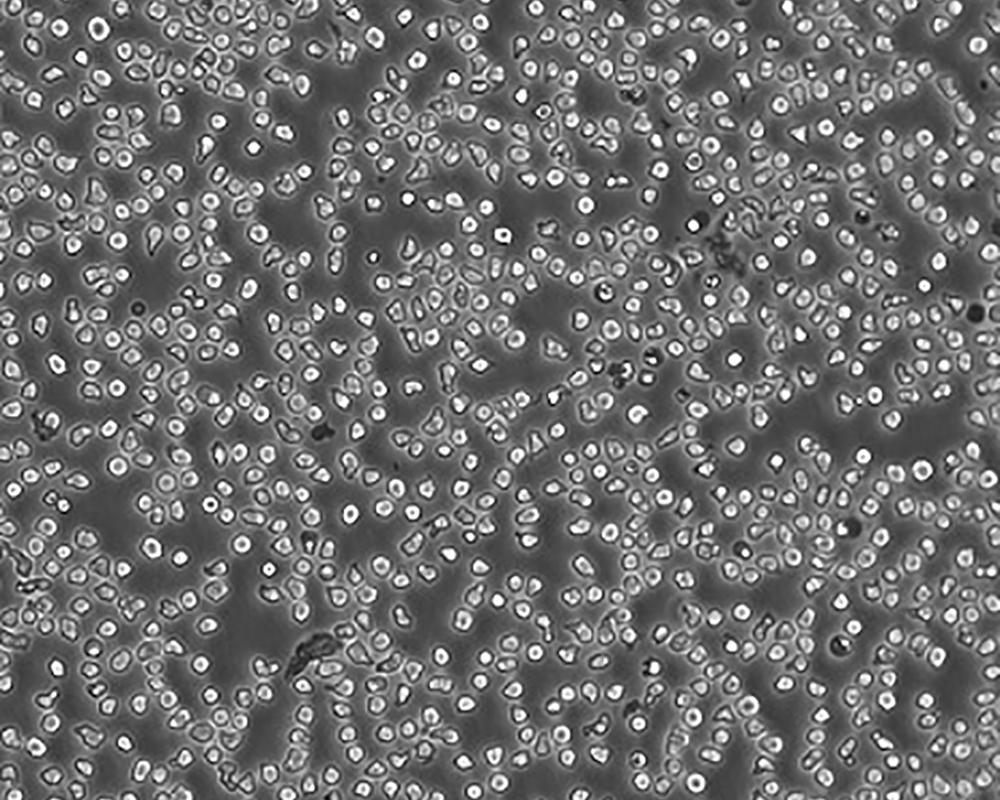

生長(zhǎng)特性 suspension

形態(tài)特征 lymphoblast

傳代方法 Maintain cell density between 2×10^4 and 4×10^4 viable cells/mL.

細(xì)胞描述 一位套細(xì)胞淋巴瘤患者的巨細(xì)胞變種顯示白血病轉(zhuǎn)變,從其外周血單核細(xì)胞出發(fā)建立了MCL細(xì)胞株JeKo-1。 JeKo-1細(xì)胞EB病毒陰性,并表達(dá)一種B細(xì)胞表型的IgM。 細(xì)胞過表達(dá)cyclin D1, Bcl-2, c-Myc 及 Rb 蛋白。 Bcl-1/J(H)基因重排得到了PCR證實(shí)。 JeKo-1細(xì)胞在SCID小鼠中高成瘤。 [PubMed: 9753063]